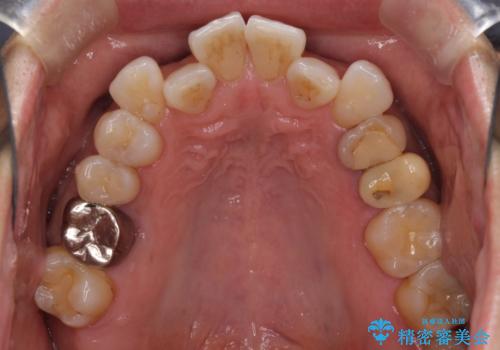

- 2年ほど放置していた左上の仮歯がとれたことをきっかけにご来院された患者様です。

セラミック治療がご希望でしたが、ときどき歯肉が腫れるということで根管治療もご希望されました。

左上の仮歯を2年使用して穴があいて外れたことをきっかけにご来院されました。

レントゲン上からも、歯の中(根管)が汚れている可能性があることをご説明したところ、根管治療からやり直しをすることになりました。